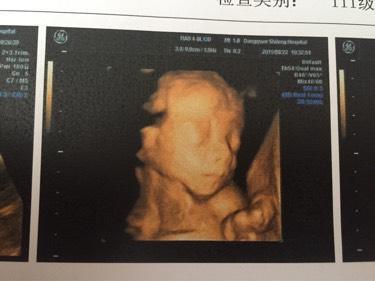

今天四维大排畸归来,医生说一切正常,终于放心了。宝宝超级配合,二十分钟就过了,贴心小棉袄,一看照片就觉得像女宝,熟人告诉我宝宝像妈妈,喜得小公主一枚,下面我就把我怀孕的一些症状整理分享给大家,接女宝宝啦!

秀秀我的小棉袄

四维